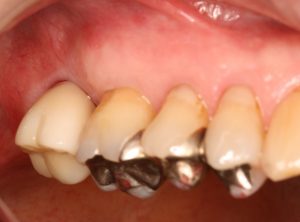

インプラント 右上4567 川口で精密インプラントなら さかえ歯科

川口で精密インプラント治療なら さかえ歯科クリック